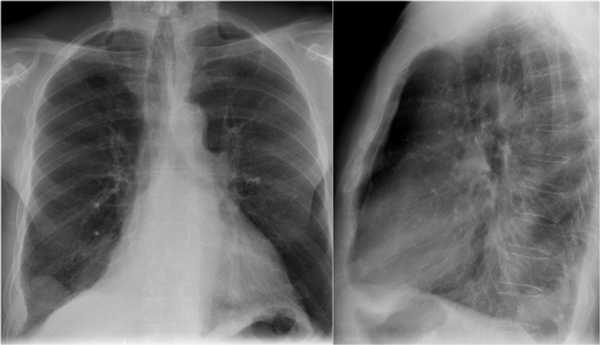

Ателектаз верхней доли левого легкого с типичным симптомом воздушного серпа (Luftsichel sign — luft(air)+sichel(sickle)), обусловленный гипервентиляцией верхнего сегмента нижней доли левого легкого на фоне коллапса верхний доли левого легкого. Гипервентилируемый

сегмент визуализируется на прямой рентгенограмме от дуги аорты до апикальной части легкого.

- В левом легком патологические изменения высокой плотности с потерей силуэта контуров сердца.

- Высокое стояние диафрагмы левого легкого.

- Смещение вниз косой щели.

- Низкое расположение правого корня легкого.

Данные изменения характерны при тотальном ателектазе верхней доли левого легкого и частичный ателектаз правого легкого. Так контуры сердца справа хорошо визуализируются то, можно сказать, что частичный ателектаз не средней доли, а нижней доли правого легкого.